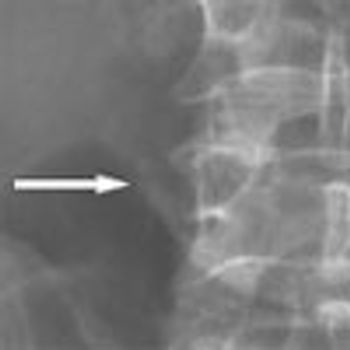

An obese 61-year-old man with a history of heroin abuse was brought to the hospital after he had fallen onto his buttocks on a sidewalk. He was able to stand initially, but weakness and numb-ness in his legs rendered him suddenly unable to walk or prevent himself from voiding. He denied abdominal or back pain. His medical history included asthma, chronic obstructive pulmonary disease, and hypertension.